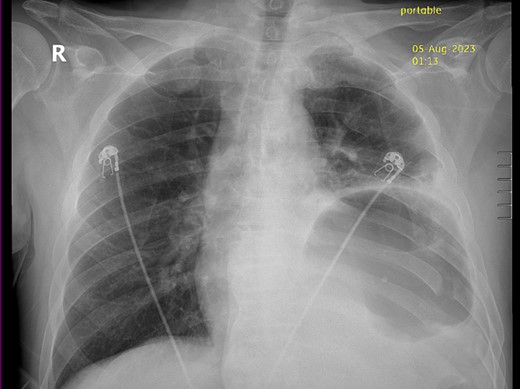

Thirty-seven days after the initial visit, the patient returned to the emergency department with burning epigastric pain that radiated to the left upper chest and hematemesis. Vital signs revealed tachycardia and hypertension. A comprehensive physical exam was significant for decreased breath sounds at the left base and tenderness in the left upper quadrant without signs of peritonitis. Pertinent laboratory findings showed leukocytosis with a left shift and thrombocytosis. A chest X-ray showed a significant portion of the gastric body in the left hemithorax (Fig. 1). A pulmonary CT angiogram found segmental and subsegmental pulmonary emboli in both lungs with no evidence of right heart strain and a left pleural effusion. A left diaphragmatic hernia with the “dangling diaphragm” sign can be seen on the sagittal view (Fig. 2). The coronal view shows discontinuity of the diaphragm and the “collar” sign (Fig. 3); the axial view shows the “dependent viscera” sign and thoracic fluid abutting abdominal viscera (Fig. 4).

Sagittal CT showing gastric body herniating through diaphragmatic defect and the “dangling diaphragm” sign (arrow).